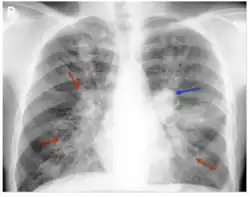

Consolidation and mucoid impaction are the most commonly described radiological features described in ABPA literature, though much of the evidence for consolidation comes from before the development of computed tomography (CT) scans. Tramline shadowing, finger-in-glove opacities, and 'toothpaste shadows' are also prevalent findings.[28]

When using high-resolution CT scans, there can be a better assessment of the distribution and pattern of bronchiectasis within the lungs, and hence this is the tool of choice in the radiological diagnosis of ABPA. Central (confined to medial two-thirds of the medial half of the lung) bronchiectasis that peripherally tapers bronchi is considered a requirement for ABPA pathophysiology, though in up to 43% of cases, there is a considerable extension to the periphery of the lung.[1]

Mucoid impaction of the upper and lower airways is a common finding.[1] Plugs are hypodense but appear on CT with high attenuation (over 70 Hounsfield units[29]) in up to 20% of patients. Where present it is a strong diagnostic factor of ABPA and distinguishes symptoms from other causes of bronchiectasis.[11]

CT scans may more rarely reveal mosaic-appearance attenuation, centrilobular lung nodules, tree-in-bud opacities, and pleuropulmonary fibrosis (a finding consistent with CPA, a disease with ABPA as a known precursor).[1] Rarely other manifestations can be seen on CT scans, including military nodular opacities, perihilar opacities (that mimic hilar lymphadenopathy), pleural effusions and pulmonary masses. Cavitation and aspergilloma are rarer findings, not exceeding 20% of patients, and likely represent a shift from ABPA to CPA if accompanied by pleural thickening or fibrocavitary disease.[11]